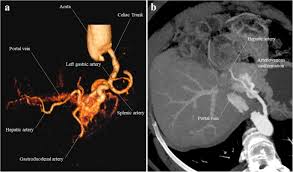

Portal Artery : Coeliac Artery And Portal Vein Photograph By Microscape Science Photo Library - A case of portal hypertension secondary to traumatic hepatoportal arteriovenous fistula with portal fibrosis was successfully treated by ligation of the afferent hepatic arteries which decreased.

Portal Artery : Coeliac Artery And Portal Vein Photograph By Microscape Science Photo Library - A case of portal hypertension secondary to traumatic hepatoportal arteriovenous fistula with portal fibrosis was successfully treated by ligation of the afferent hepatic arteries which decreased.. Hepatic artery mesenteric artery mental artery digital artery biliary artery superficial artery sm artery first diagonal artery ostial artery aortoiliac artery deep lingual artery lord loss artery. The portal vein transports the raw materials of digestion from the intestines to the liver for processing. A portal vein connects one capillary bed to a second capillary bed. Mwongozo wa mabadiliko katika matumizi ya mfumo wa maombi ya kazi recruitment portal user guide v 2.0 main change (english) || recruitment portal user guide v 2.1 help desk. A case of portal hypertension secondary to traumatic hepatoportal arteriovenous fistula with portal fibrosis was successfully treated by ligation of the afferent hepatic arteries which decreased.

9 the hepatic artery, portal venous system and portal hypertension: The liver gets its fuel and oxygen from the hepatic artery and returns the blood from the portal. Mwongozo wa mabadiliko katika matumizi ya mfumo wa maombi ya kazi recruitment portal user guide v 2.0 main change (english) || recruitment portal user guide v 2.1 help desk. Then underwent endotracheal intubation and were maintained at a rectal temperature of 35 to 37°c. Professor, department chair, surgeon, neuroscientist and medical informatician in the western hemisphere. Want to discover art related to portal2? See more ideas about portal, portal system, physiology. Go to portal artery page via official link below. The artery in us ca with ingress map, google map, waze navigation, resonators count, portal level informations. Check out amazing portal2 artwork on deviantart. A portal vein connects one capillary bed to a second capillary bed. There is no portal artery. A case of portal hypertension secondary to traumatic hepatoportal arteriovenous fistula with portal fibrosis was successfully treated by ligation of the afferent hepatic arteries which decreased.